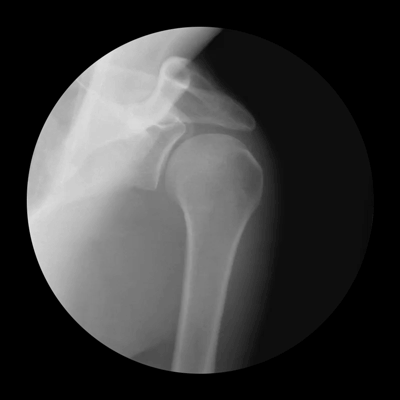

Οι παρακάτω φωτογραφίες, για την ακρίβεια πρόκειται για ακτινογραφίες του ορθοπεδικού Noah Weiss ο οποίος σε συνεργασία με τον φωτογράφο Cameron Drake, δημιούργησαν αυτές τις εκπληκτικές απεικονίσεις. Με τον τρόπο τους, ρίχνουν φως στο τι συμβαίνει στις αρθρώσεις.